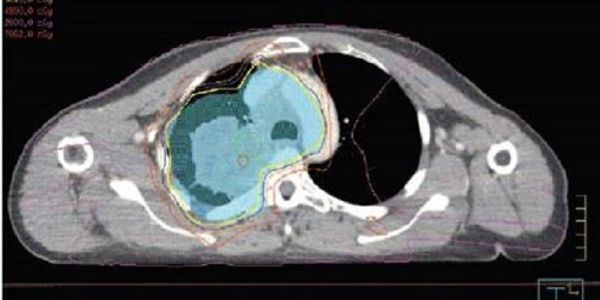

Scientists have been awarded £900,000 from Cancer Research UK to launch a groundbreaking clinical trial for people with lung cancer.

Scientists have been awarded £900,000 from Cancer Research UK to launch a groundbreaking clinical trial for people with lung cancer.

Gold nanotubes – tiny hollow cylinders one thousandth the width of a human hair – could be used to treat mesothelioma, a type of cancer caused by exposure to asbestos fibres, say researchers.